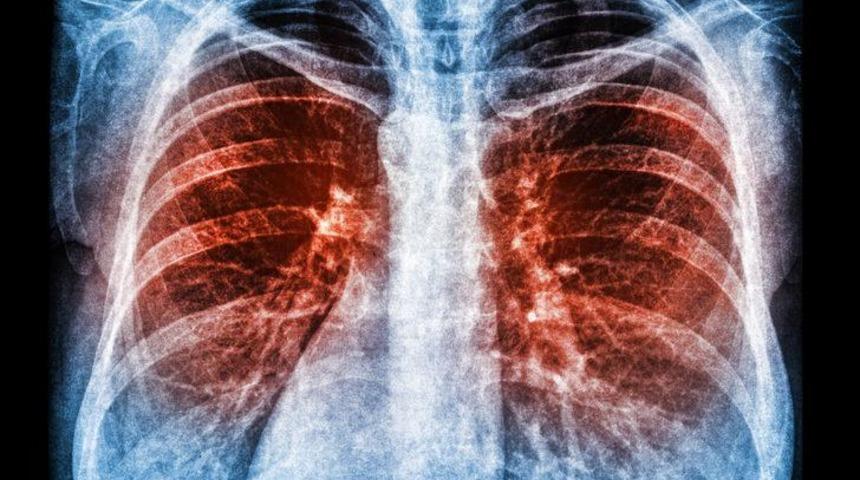

Verem Savaş Dispanseri'nde görevli Dr. Yüksel Oğuz, veremin öksürükle bulaşan bir enfeksiyon hastalığı olduğunu söyledi.

ÖKSÜRÜKLE BAŞLIYOR

Verem Savaş Dispanseri'nde görevli Dr. Yüksel Oğuz ise, veremin öksürükle bulaşan bir enfeksiyon hastalığı olduğunu belirterek, "Genel olarak öksürükle bulaşan verem kan, yeme-içme, cinsel ilişki, tokalaşma ve elbiseler yoluyla bulaşmıyor. Veremde risk grubunu, veremli hastanın ailesi, veremli hasta ile 72 saatten uzun bir süre aynı ortamda kalanlar, küçük çocuklar, cezaevlerinde kalanlar, bağışıklık sistemi zayıf olanlar oluşturuyor. Vücut direnci güçlü olanlar hastalığı kolay yenebiliyorlar. Veremin belirtileri ise balgam, gece terlemesi, öksürük, zayıflık, ateş, nefes darlığı, yan ağrısı, balgamdan kan gelmesi şeklinde ortaya çıkıyor. 2-3 haftadan uzun süre bu belirtilerin görülmesi halinde hastanın mutlaka Verem Savaş Dispanseri'ne başvurması gerekiyor" diye konuştu.